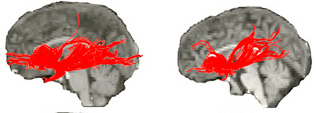

Diffusion tensor imaging, which by detecting the flow of water in nerve fibers can identify and measure the connections between brain areas, showed reduced white matter – the brain’s long-distance wiring – between thinking and emotion hubs.

Tracking radioactively-tagged water in order to measure brain blood flow at rest, via positron emission tomography (PET), exposed activity aberrations consistent with the MRI abnormalities. The PET scans also revealed altered functional coupling between the front of the insula and key structures involved in thinking, mood and fear processing. These structural and functional abnormalities in the front of the insula correlated with the Williams syndrome personality profile.